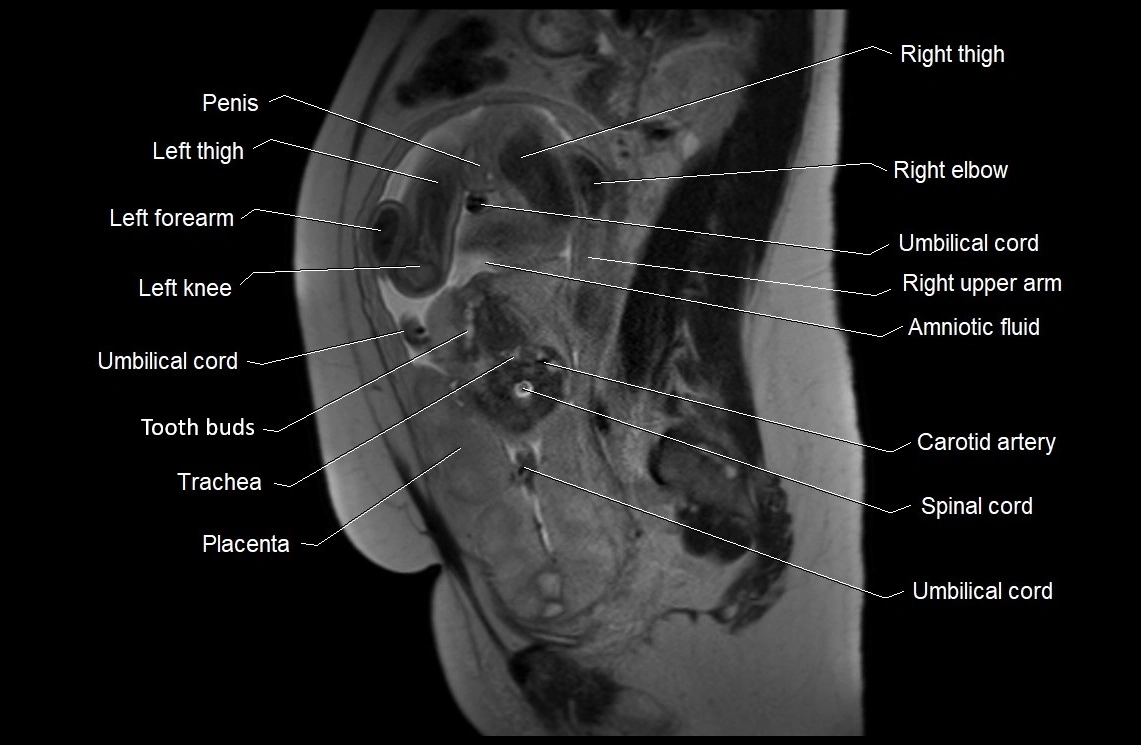

MRI Appearance

T2 HASTE (T2 GRE):

• Amniotic fluid shows very bright hyperintense signal

• Provides natural contrast against fetus and placenta

• Small particles (vernix) may appear as scattered hypointense foci within bright fluid

T1 GRE:

• Amniotic fluid shows low signal intensity (dark)

• Hemorrhage, infection, or proteinaceous content may cause focal or diffuse high signal intensity